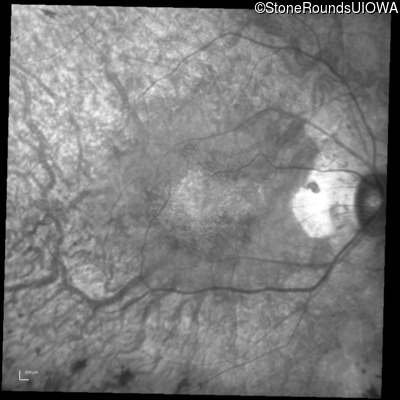

Infrared Fundus Photograph - Left - 20/20 -2

Exemplar